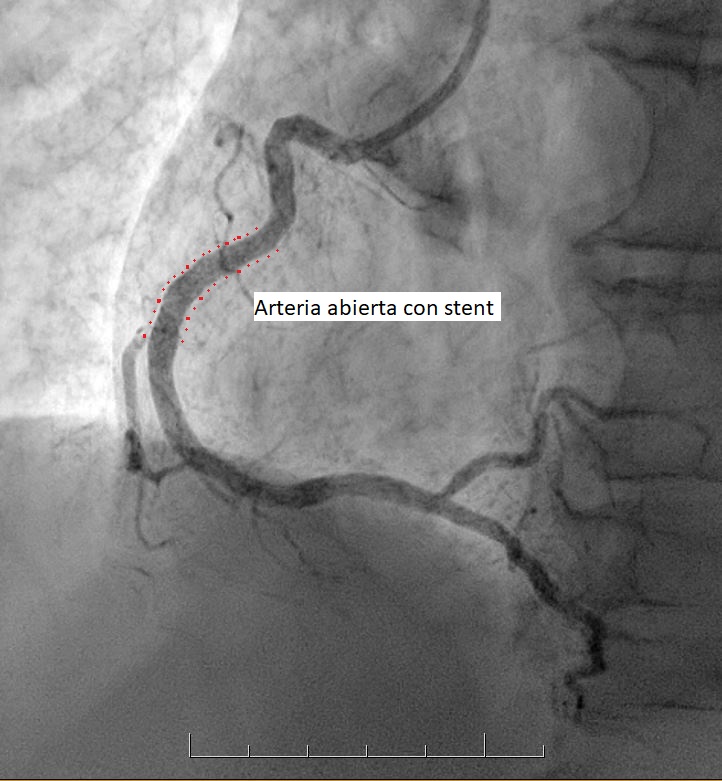

• Es un procedimiento que permite eliminar las obstrucciones de las arterias, abriendo el paso a la circulación de la sangre y dejando lugar para la colocación de un stent.

• Es un pequeño tubo de malla metálica que, una vez ubicado en la arteria, se expande y queda adherido a sus paredes, reforzando el procedimiento de desobstrucción. Se utiliza, en la mayoría de los casos, como complemento de la angioplastía y da muy buenos resultados.

Este catéter llega hasta las arterias que se van a tratar y una vez allí se inyecta una sustancia de contraste, que permite visualizar las obstrucciones existentes. A través de este catéter se inserta un balón, que se expande en el sitio obstruido y luego se retira, dejando lugar para la colocación de un stent.